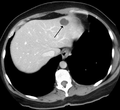

The majority of infantile hemangiomas (IH) can be diagnosed by history and physical exam.[6] In rare cases, imaging (ultrasound (US) with Doppler, magnetic resonance imaging (MRI)) and/or cytology or histopathology are needed to confirm the diagnosis.[28][18] IH are usually absent at birth or there may be a small area of pallor, telangiectasias, or duskiness. A fully formed mass at birth usually indicates a diagnosis other than IH. Superficial hemangiomas in the upper dermis have a bright red strawberry color, whereas those in the deep dermis and subcutis, deep hemangiomas, may appear blue and be firm or rubbery on palpation. Mixed hemangiomas can have both features.[6] A minimally proliferative IH is an uncommon type of IH that presents with fine macular telangiectasias with an occasional bright-red, papular, proliferative component. Minimally proliferative IH are more common in the lower body.[29]

If the diagnosis is not clear based on physical exam and growth history (most often in deep hemangiomas with little cutaneous involvement), then either imaging or histopathology can help confirm the diagnosis.[28][4] On Doppler ultrasound an IH in the proliferative phase appears as a high flow soft-tissue mass usually without direct arteriovenous shunting. On MRI, IH show a well-circumscribed lesion with intermediate and increased signal intensity on T1 and T2-weighted sequences, respectively, and strong enhancement after gadolinium injections. There are fast flow vessels.[28] Tissue for diagnosis can be obtained via fine needle aspiration, skin biopsy, or excisional biopsy.[30] Under the microscope, hemangiomas are unencapsulated aggregates of closely packed, thin-walled capillaries, usually with endothelial lining. Blood-filled vessels are separated by scant connective tissue. Their lumens may be thrombosed and organized. Hemosiderin pigment deposition due to vessel rupture may be observed.[31] The GLUT-1 histochemical marker can be helpful in distinguishing IH from other items on the differential diagnosis, such as vascular malformations.[18]